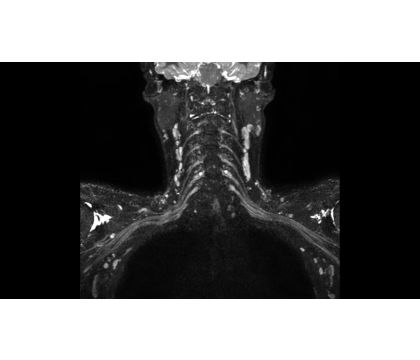

3D NerveVIEW improves visualization of the brachial and lumbar plexus by providing you with a high resolution T2w TSE acquisition with reduced remaining intra-lumen signal of the veins¹. In addition, the 3D isotropic imaging method allows for reformats in any plane (including oblique) without loss of resolution helping you to save scan time and improve spinal nerve plexuses assessment.

• 3D NerveVIEW (oblique reformat)

3D NerveVIEW (oblique reformat)

• 3D NerveVIEW

3D NerveVIEW

• 3D NerveVIEW (right oblique reformat)

3D NerveVIEW (right oblique reformat)